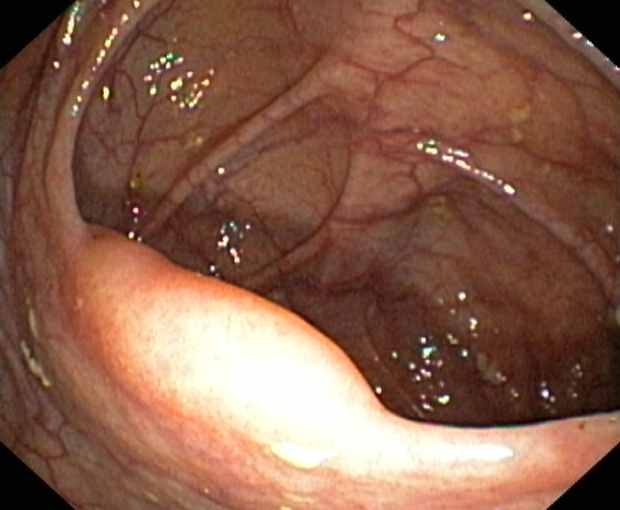

Ileocaecal valve